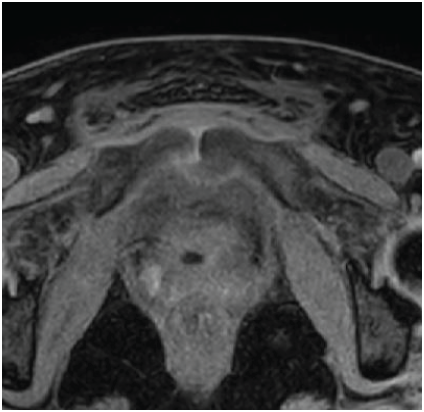

A 42-year-old South Asian woman with a history of hypothyroidism and recurrent UTIs presented with a 2-week history of lower abdominal pain radiating to both lower limbs, associated with high-grade intermittent fever. The pain was spontaneous in onset, progressive, and unrelated to trauma. She had previously received multiple short courses of antibiotics for recurrent UTIs. She presented to our center 10 days after the onset of symptoms. On evaluation, she was febrile (temperature 102°F), with suprapubic tenderness and restriction of active and passive hip movements bilaterally. Initial laboratory investigations revealed neutrophilic leukocytosis (total leukocyte count: 15,000/µL; neutrophils: 13,600/µL) and elevated C-reactive protein (195 mg/L). Urine routine examination demonstrated numerous red blood cells but no pyuria. A contrast-enhanced computed tomography renal stone survey showed perinephric stranding in the retropubic space suggestive of cystitis, with no evidence of collections, hematoma, or pelvic bone fractures. She was empirically started on intravenous piperacillin-tazobactam for presumed acute cystitis, given her history of recurrent UTIs. However, urine culture showed no growth after 48 h, while blood cultures grew MRSA. Antibiotics were escalated to intravenous teicoplanin (400 mg twice daily). Despite 48 h of appropriate therapy, she continued to have high-grade fever and worsening excruciating suprapubic pain radiating to the groin and medial thighs, severely limiting her mobility. Magnetic resonance imaging (MRI) of the pelvis with contrast revealed osteomyelitis of the bilateral pubic bones and superior pubic rami, with abscesses (10 mL and 1.5 mL) around the pubic symphysis, fluid collections in the right adductor and obturator externus muscles, and edema of the obturator internus, externus, and pectineus muscles (Figs. 1, 2, 3, 4).

Figure 1: Axial T2-weighted magnetic resonance imaging of the pelvis showing marrow edema and signal alteration involving the bilateral pubic bones and superior pubic rami, consistent with osteomyelitis.

Figure 4: Axial T1-weighted magnetic resonance image of the pelvis showing altered marrow signal intensity involving the bilateral pubic bones and superior pubic rami, consistent with osteomyelitis. The pubic symphysis appears widened with adjacent soft-tissue edema and early abscess formation. Surrounding muscular edema is noted in the adductor and obturator groups.